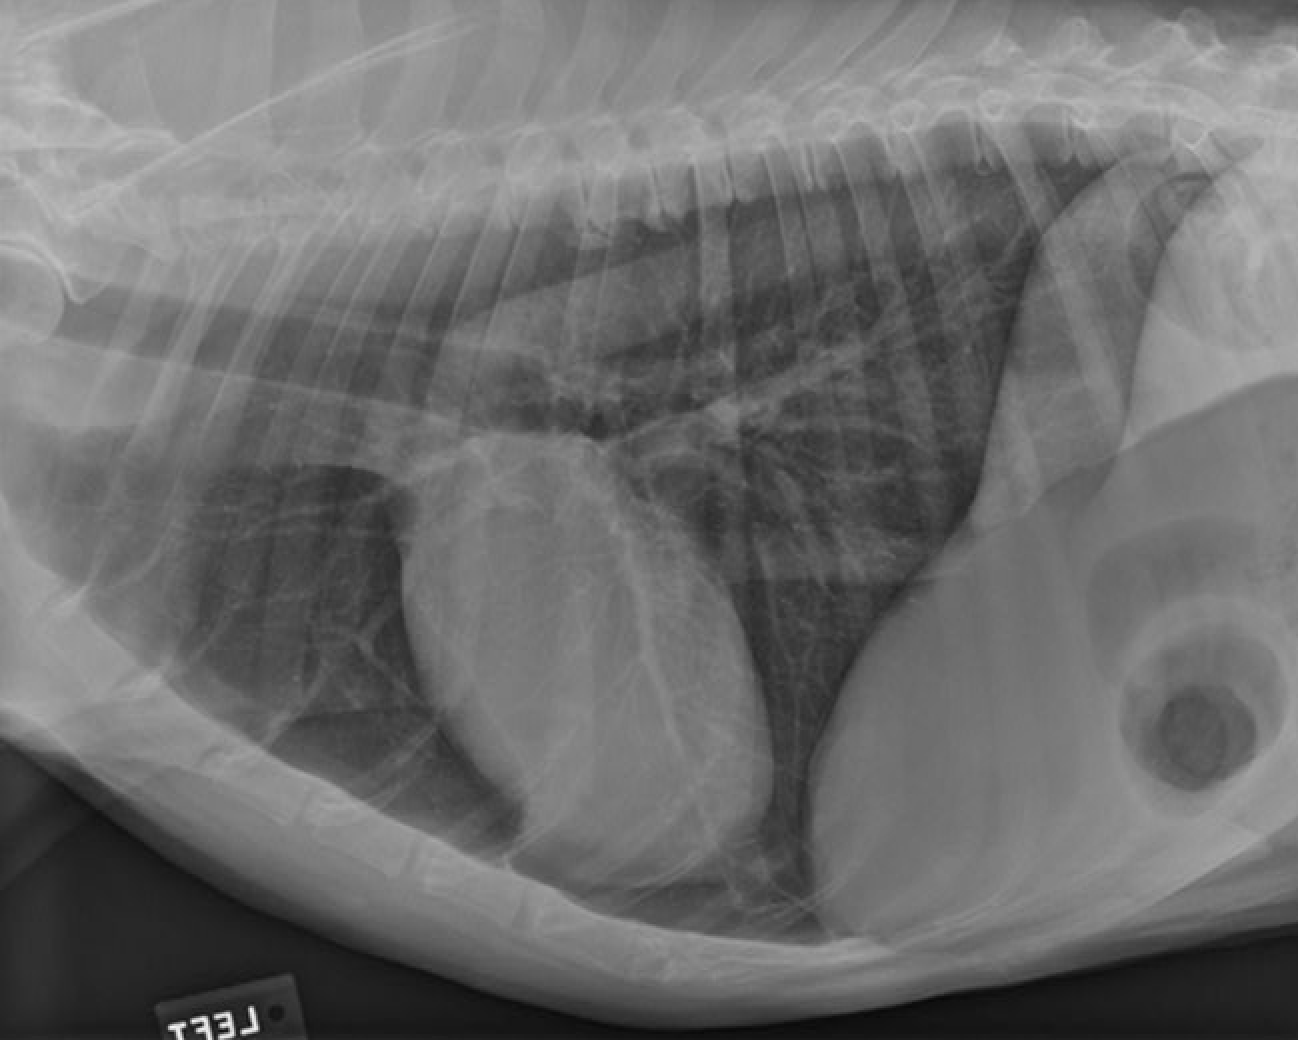

identify A, B and C

A= left atrium

B= right ventricle

C= trachea

identify the structures

RA: right auricle (atrium)

RV: right ventricle

LV: left ventricle

LA: left atrium

A: aorta

C: caudal vena cava

T: trachea